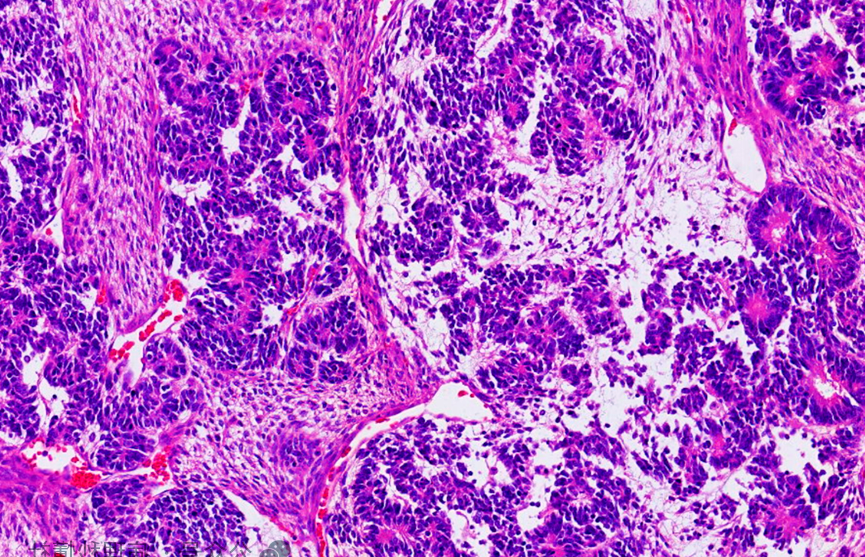

肾母细胞瘤在儿童肾脏恶性肿瘤中非常常见(资料图)

肾母细胞瘤多见于3至5岁儿童,这个年龄段的患者治愈率相对较高。而婷婷确诊时已10岁,且病情发展迅速。据医生介绍,该病多与基因缺陷或身体隐匿性疾病相关,部分患儿的病情可能终生不爆发,而婷婷不幸成为了发病的那一个。